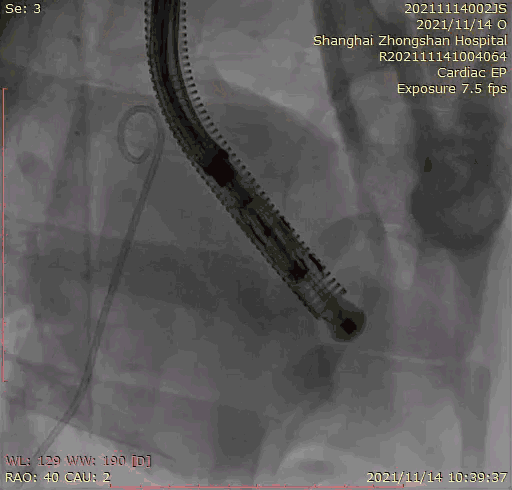

本次臨床前研究經右側頸靜脈置入LuX-Valve Plus輸送系統可調彎鞘管,在DSA及超聲引導下將人工三尖瓣瓣膜植入到原有三尖瓣位置,利用獨特的錨定技術將人工瓣膜支架可靠固定在預定的位置。

上海中山醫院葛均波院士、錢菊英院長、周達新教授、潘文志教授、潘翠珍教授、李偉教授共同完成此次臨床前研究。術后葛均波院士對Lux-Valve Plus的器械操作性能給予了高度評價,DSA和超聲影像也顯示出在本次研究中Lux-Valve Plus的安全性和有效性俱佳。